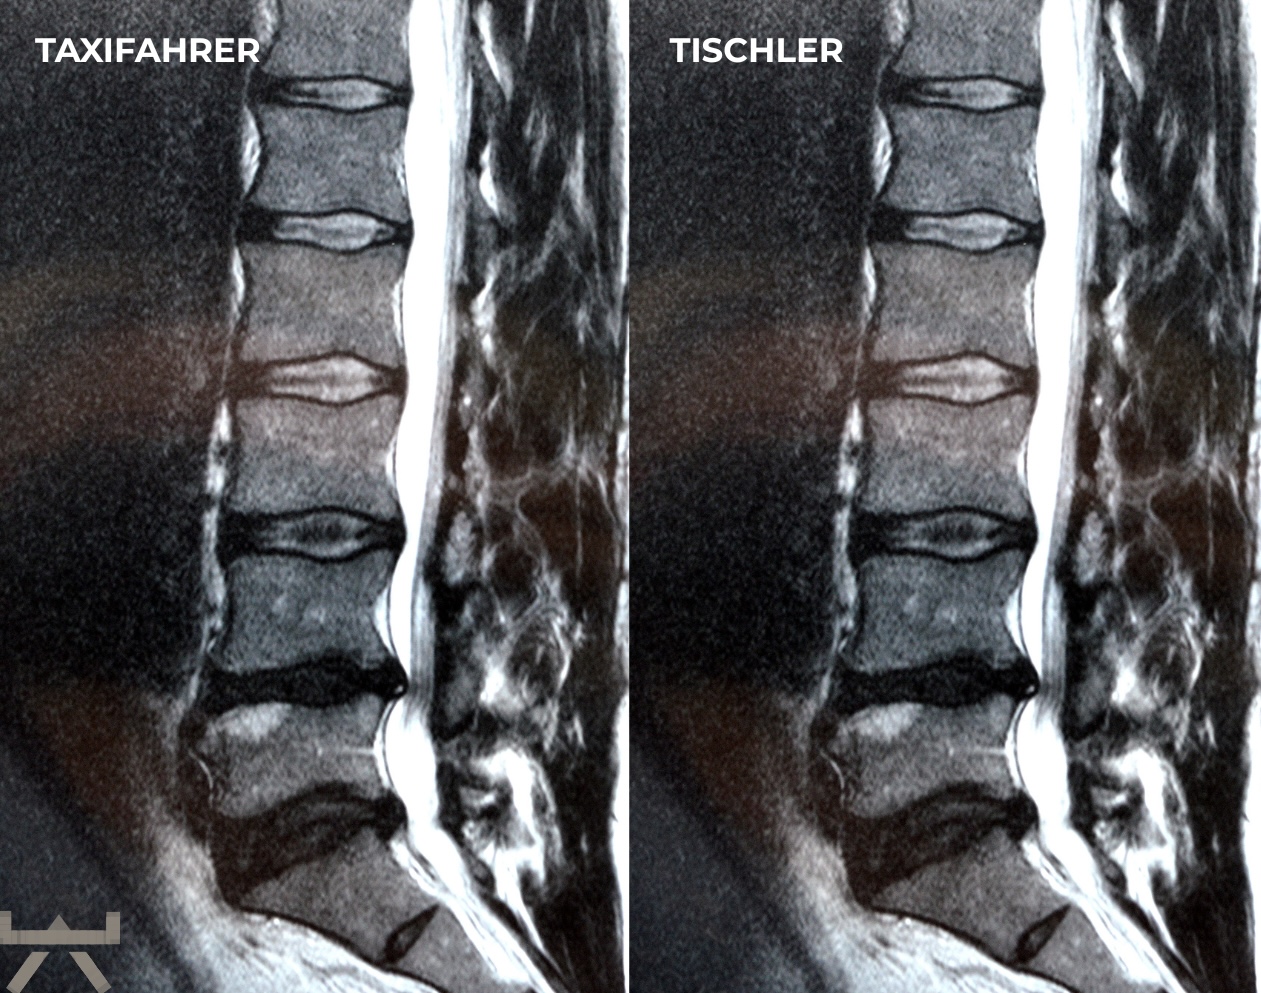

Arthrose wird durch schwere Arbeit verursacht.

Viele machen ihre Arbeit oder ihren Sport für Arthrose verantwortlich, obwohl die meisten Forschungsergebnisse feststellen, dass unsere beruflichen und freizeitlichen Aktivitäten einen relativ geringen Einfluss auf strukturelle Veränderungen haben. Eine der interessantesten Möglichkeiten, dies zu demonstrieren, sind MRT-Studien an schmerzfreien genetisch eineiigen Zwillingen, die aber sehr unterschiedliche berufliche und freizeitliche Aktivitätsniveaus haben, und trotzdem sehr ähnlich aussehende Scans aufweisen. Studien zeigen uns diesbezüglich, dass eine Wirbelsäule, die den größten Teil des Tages sitzt, jener bemerkenswert ähnlichsieht, welche den ganzen Tag schwere Arbeit leisten muss. 11